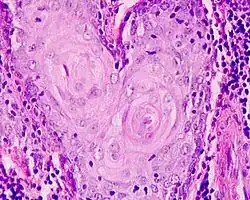

Es wird insbesondere in der Histologie zum Färben von Zell- und Gewebestrukturen, wie z. B. Zellkernen, Mitochondrien, Myelin, Elastin und Kollagenfasern eingesetzt. Darüber hinaus fand Hämatoxylin in der Färberei und in der Tintenproduktion Anwendung.

Histologie

In der Histologie wird Hämatoxylin zum Färben von Zell- und Gewebestrukturen, wie z. B. Zellkernen, Mitochondrien, Myelin, Elastin und Kollagenfasern eingesetzt.[3] Zahlreiche Varianten der Hämatoxylinfarblösungen wurden entwickelt, die sich insbesondere in der Hämatoxylinkonzentration, der Wahl des Oxidationsmittels sowie der Wahl des Kations (Beize) und somit im Färbeverhalten unterscheiden. Beispiele hierfür sind die Farblösungen nach Harris, Ehrlich, Mayer, Weigert, Heidenhain und Verhoeff.

In Kombination mit der Hämatoxylin-Färbung (Zellkernfärbung) wird in der Regel eine Gegenfärbung mit einem kontrastreichen Zytoplasmafarbstoff durchgeführt. Klassisch wird eine Gegenfärbung mit Eosin durchgeführt (Hämatoxylin-Eosin-Färbung), bei der kationische/eosinophile Strukturen (z. B. Proteine) angefärbt werden. Hierbei werden Zellkerne üblicherweise dunkelblau eingefärbt, während die anderen Zellbestandteile hellrosa bis pink erscheinen. Für die HE-Färbung werden Hämalaune eingesetzt. Bei Bindegewebsfärbungen (z. B. Van-Gieson-Färbung, Masson-Trichrom-Färbung) findet man üblicherweise die Eisenhämatoxylinlösung nach Weigert in Kombination mit anderen sauren Farbstoffen (z. B. Pikrofuchsin, Anilinblau, Orange G, Säurefuchsin, u. v. m.). Bei der Immunohistochemie wird eine Kernfärbung mit Hämalaun als Gegenfärbung angeschlossen. Das Färbeergebnis zeigt hier positive Reaktionen in rötlich-braun (DAB) mit zart-blauen Kernen.